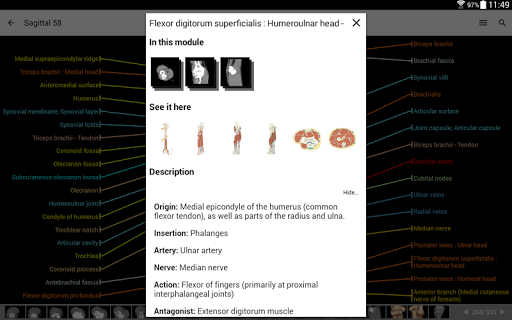

* تحسين عرض التفاصيل للأجزاء التشريحية لتسهيل التعرف عليها في صور الوحدات الحالية والوحدات الأخرى.

* تحسين رؤية تعريفات الأجزاء التشريحية

* تصفح بين الأجزاء التشريحية باستخدام روابط الوصف

- يتم الآن عرض المصطلحات المتعلقة بالهيكل التشريحي في عرض التفاصيل - تمت إضافة

- يتميز وضع الدبابيس بسلوك جديد يسمح لك باتباع بنية تشريحية بسهولة أكبر

- ضمن عرض التفاصيل للبنية التشريحية ، يشير الدبوس الآن إلى البنية ذات الصلة في جميع الصور الحالية

انقر أيضًا مباشرة على الصورة للانتقال إلى الصورة المعروضة في تلك الوحدة

- خيار جديد لتوسيع معارض الصور في شاشة معلومات الهيكل التشريحي.

- يمكنك الآن إخفاء الهياكل واحداً تلو الآخر (زر جديد داخل نافذة الوصف المنبثقة) وعرضها مرة أخرى في القائمة الصحيحة